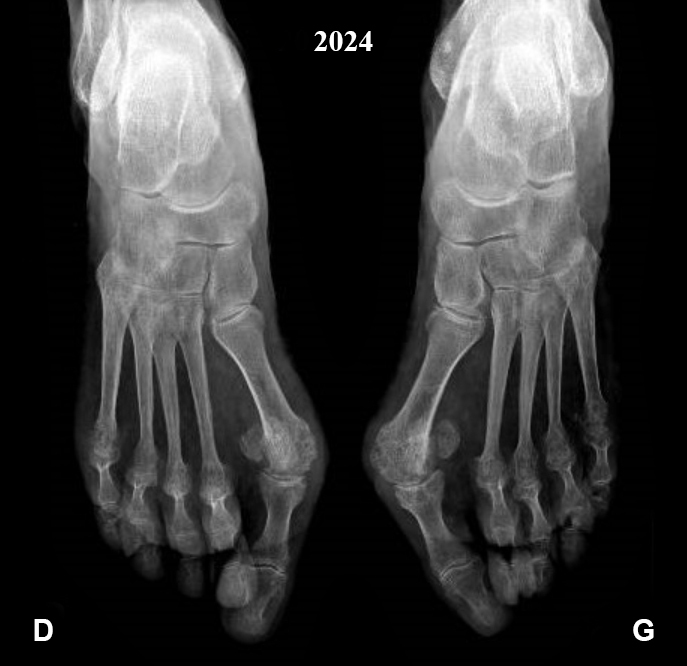

Elle vous montre sa dernière prise de sang avec une protéine C réactive (CRP) à 45 mg/L et vous apporte ses dernières radiographies (fig. 2), que vous comparez aux précédentes (fig. 1).

Figure 1 (Source Salomé Abdellaoui, La Revue du Praticien)

On observe sur la radiographie de 2024 un pincement articulaire de toutes les articulations métatarso-phalangiennes avec des subluxations de ces dernières et des érosions de la tête des 5es métatarsiens, caractéristiques de la polyarthrite rhumatoïde.